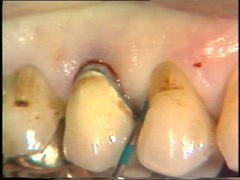

Limpieza subgingival de las raíces.

El tratamiento inicial consiste en el raspado y alisado radicular subgingival  bajo  anestesia local. Como resultado de este tratamiento el margen  gingival se ha retraído. Sin embargo en la región de la furcación las señales de patología permanecían y las profundidades de bolsa al sondaje  todavía eran 6 mm o más en cada una de las raíces.

En el  segundo premolar las profundidades de bolsa al sondaje no se han modificado después del tratamiento inicial. También mostraron sangrado y salida de  pus de la superficie bucal  durante el sondaje periodontal.

Del lado palatino puede observarse que la lesión de furcación  ha sido  expuesta y que la patología todavía es prominente. Las profundidades al sondaje son de  6-8 mm, excepto en el sitio palatino  del primer molar dónde la bolsa  es bastante poco profunda.

El tejido gingival parece saludable en palatino de los incisivos.  Sin embargo, al sondaje periodontal revela  inflamación persistente y flujo de pus en las bolsas que tienen  6-8 mm  de profundidad;  se  indica la necesidad de cirugía por colgajo para tener un mejor acceso a la superficie de la raíz, placa bacteriana restante y cálculo.